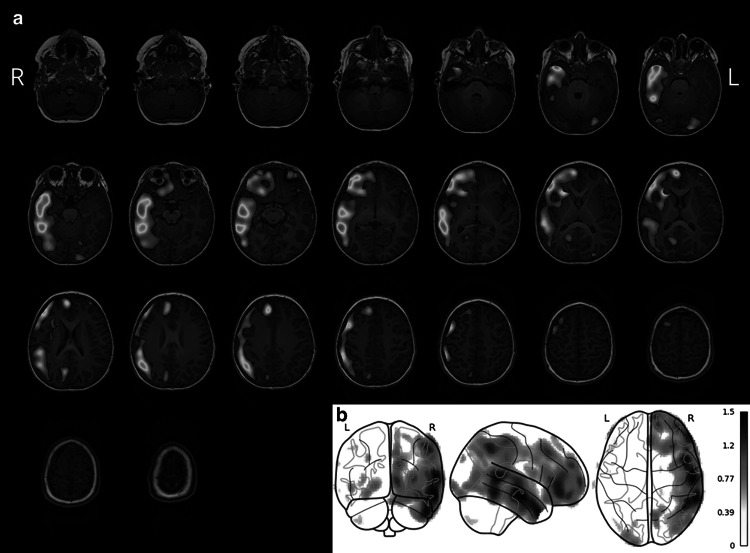

Fig. 3.

Other types of result files generated by MNI SISCOM include compact axial/coronal/sagittal slides showing only interictal/ictal SPECT or SISCOM results a and schematic maximum intensity projection (“glass brain”) images showing thresholded SISCOM maps superimposed over an anatomical reference drawing b